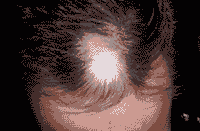

(治疗前后对比图)